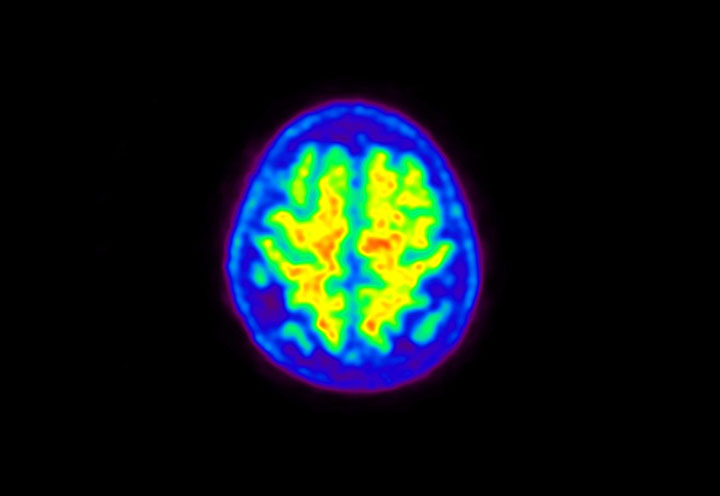

Head / Case5 : Amyloid

Coronal

Courtesy : Kindai University Hospital

- Imaging protocol

- Injected dose: 4.27 MBq/kg, 18F-Flutemetamol

- Uptake time: 99 minutes

- Scan time: 20 minutes